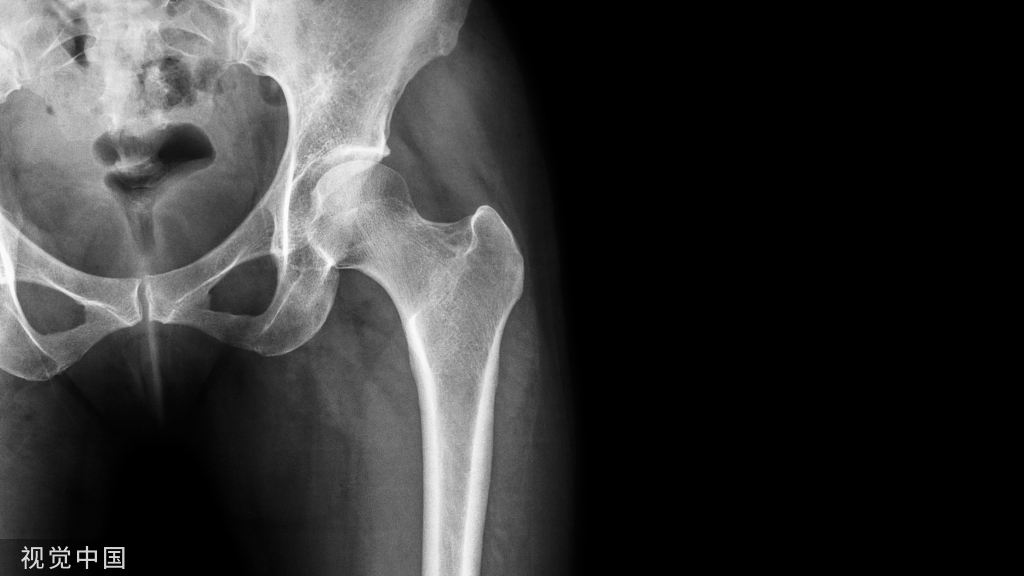

15、骨盆的软骨连接:骨盆由髂骨、坐骨和耻骨构成,未形成骨性连接之前表现为透亮线。

17、 髋臼上缘的副骨:少见。